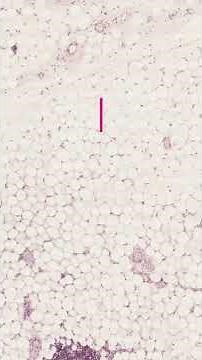

- Epithelial

Tissue Classification - Living Organism